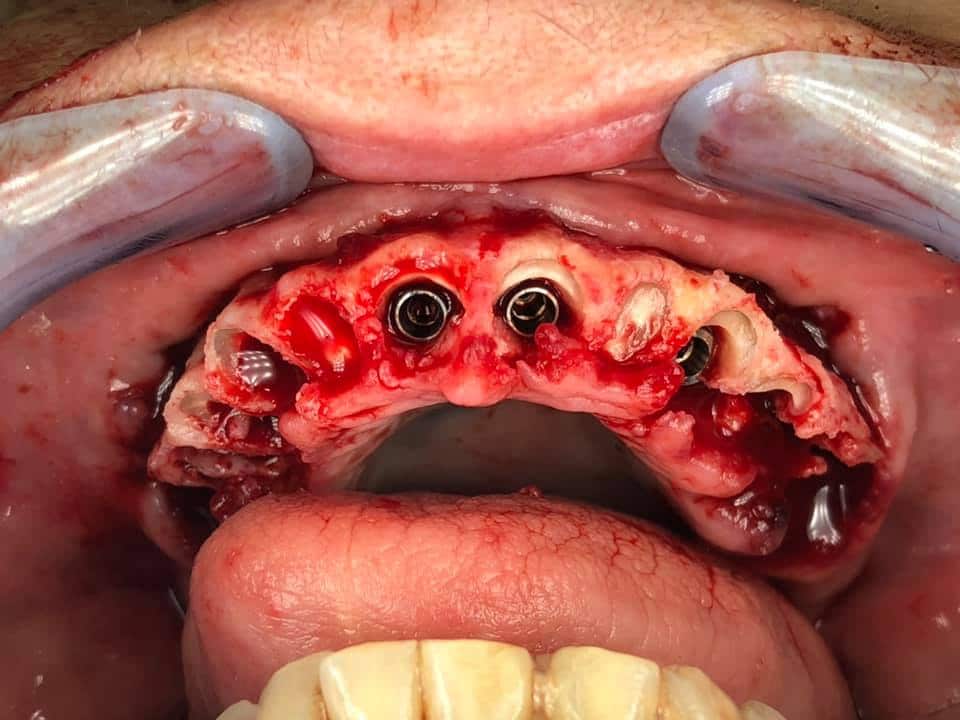

Below is a case of full arch same day temporization using the socket shield , root submergence and pontic shield techniques to preserve the site architecture . Neodent GM implants were placed in a guided fashion and same day temporization was performed using a milled PMMA.

-Immediate load temp upper